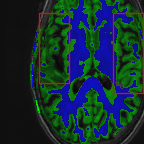

Sparsity LI 2D CNN 3D CNN Ours GT

4 Refer to caption (a) 0.6787/0.7972 Refer to caption (b) 0.8143/0.8776 Refer to caption (c) 0.8190/0.8714 Refer to caption (d) 0.8664/0.9085 Refer to caption (e) GM/WM

Refer to caption (f) 0.6808/0.7161 Refer to caption (g) 0.8103/0.8631 Refer to caption (h) 0.7950/0.8606 Refer to caption (i) 0.8598/0.9115 Refer to caption (j) GM/WM

Figure 6: Visual comparison of gray matter (Green)/white matter (Blue) segmentation over different methods, with respective DICE scores listed under the images.

In Fig. 6, we demonstrate the advantage of the proposed method in brain matter segmentation. It is clear that although 2D and 3D CNN generates visually plausible interpolation as presented in Fig. 5, the brain matters are easily misclassified due to incorrect anatomical structures and blurred details.